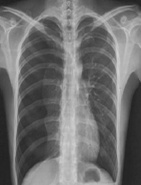

| 病史:男性,65歲,突感胸悶氣促1小時。診斷: |

| ○ 右側(cè)氣胸 | |

| ○ 右側(cè)大葉性肺炎 | |

| ○ 右側(cè)胸腔積液 | |

| ○ 肺結(jié)核 | |

| ○ 右側(cè)肺癌 |